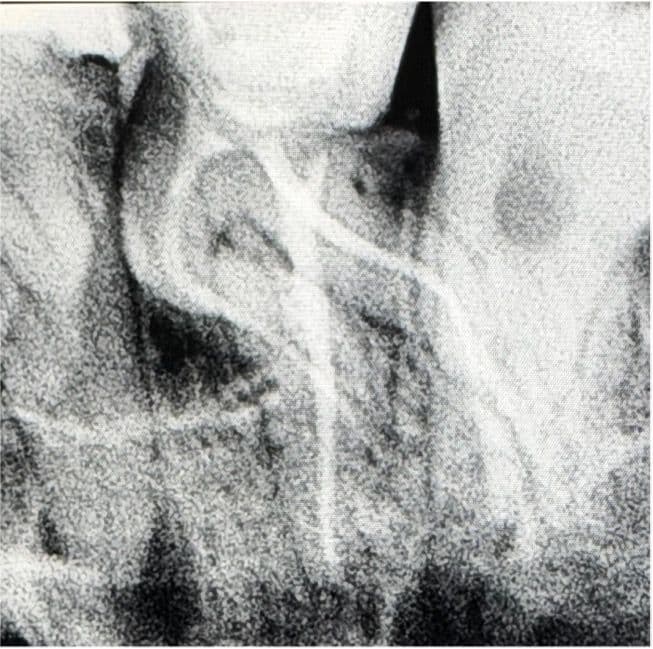

Kemomekanik Preparasyon ve İrigasyon: Kök kanallarındaki aşırı ve keskin kurvatür (eğim) nedeniyle basamak oluşumunu (ledge) ve kanal transportasyonunu önlemek amacıyla Perfect Endo Super System Advanced Kit tercih edilmiştir. Kurvatürün yarattığı anatomik zorlukları güvenle aşmak adına koruyucu bir manipülasyon tekniği uygulanmıştır. Bu doğrultuda, sistemin döner alet eğesi öncelikle manuel olarak kök kanalına yerleştirilmiştir. Eğe kanal içerisinde kurvatür yoluna uyum sağlamış durumdayken endomotora bağlanmış ve ileri yönde ritmik "zig" hareketleri yapılarak apekse kontrollü bir şekilde ilerlenmiş ve kanal genişletmesi tamamlanmıştır. Preparasyon aşamaları boyunca ana irigasyon solüsyonu olarak NaOCl kullanılmış ve temizlik etkinliğini maksimuma çıkarmak amacıyla EDDY sonik aktivasyon sistemi ile irigasyon aktivasyonu sağlanmıştır.

Kanal Dolumu: Şekillendirme ve final irigasyonunu takiben kanallar kurutulmuş ve tek seansta sızdırmaz bir şekilde üç boyutlu obturasyon işlemi gerçekleştirilmiştir. Alınan radyografilerde aşırı kurvatürlü kanalların orijinal anatomisine sadık kalındığı görülmektedir.